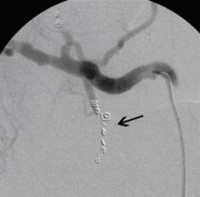

Postoperative abdominelle Blutungen bei chronischer Pankreatitis (Pfeile: Art. hepatica und Art. gastroduodenalis).

(Bild 1 von 5)